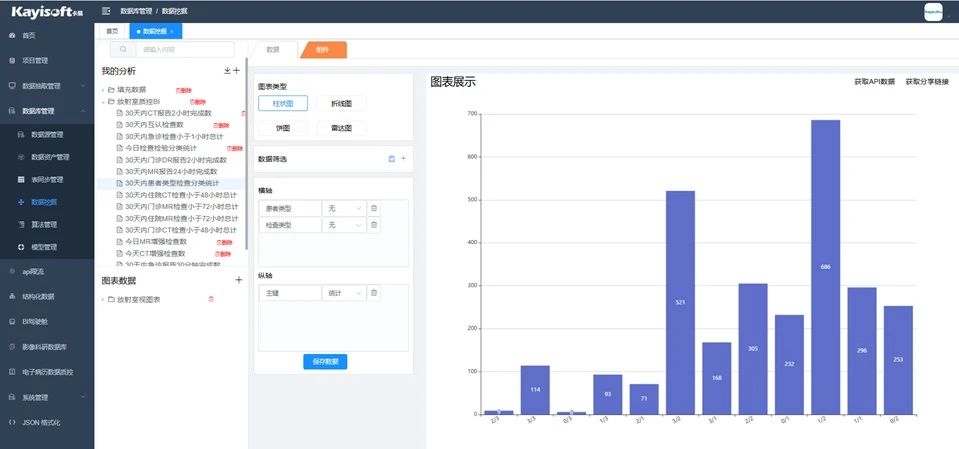

智能医疗数据治理平台通过全面且深入的数据治理功能,涵盖数据抽取、清洗、数据库管理和系统管理等关键环节,对医疗全域数据进行精细化处理,从而确保医疗数据的高质量、统一性和安全性。在此基础上,结合先进的DeepSeek技术,平台能够进一步优化数据治理流程,提升数据利用效率,实现精准、智能的医疗数据管理与应用,为医院高质量发展提供强有力的数据支撑。

平台支持复杂的数据分析和模型构建,通过强大的数据挖掘工具,用户可以进行深入的数据分析,并利用柱状图、折线图、饼图、雷达图等多种可视化方式直观展示分析结果。这不仅保障了数据的安全与合规,还为医院系统提供了强有力的支持,助力医院实现数字化转型和智能化升级。为医院提供科学的决策依据,支持实时数据分析和预测建模,使得数据治理不仅仅是技术层面的工作,而是成为医院战略的重要组成部分。